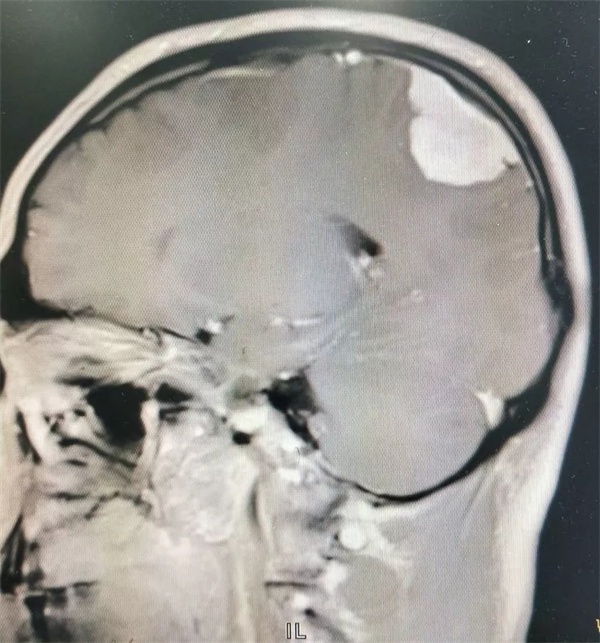

11月28日凌晨一点左右,朱某睡眠正酣,突发四肢抽搐,口吐白沫,双眼上翻,呼之不应,持续数分钟方才停止,睡在一旁的妻子目睹这一切,仿佛经历晴天霹雳,还以为丈夫“被鬼打了” 或“是中邪了”,一时间不知所措。待缓过神后还是拨打120,120把朱某送至捕鱼游戏 神经外科,头颅CT 检查提示右侧顶枕叶类圆形高密度占位,接诊医师姚勇、李世清考虑颅内占位所致继发性癫痫。